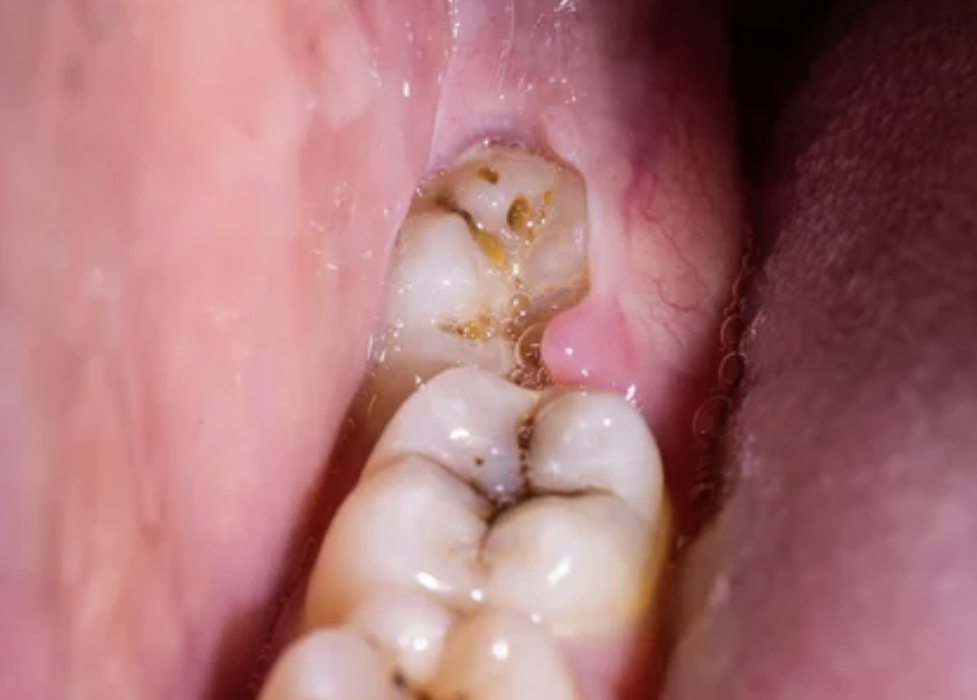

사랑니는 구강 내에 가장 안쪽에서 맹출하는 세번째 큰 어금니(제3대구치) 입니다.

영구치 중에서 가장 늦게 맹출하는 치아로, 보통 10대 후반에서 20대 초반에 나타납니다. 구강 내 공간이 부족한 경우 사랑니는 제대로 위치하지 못하거나 매복되는 경우가 있습니다. 이런 사랑니의 경우 주변 치아의 손상을 일으키거나 주변 잇몸의 통증, 염증의 원인이 될 수 있는데, 이런 경우 사랑니 발치가 필요할 수 있습니다.